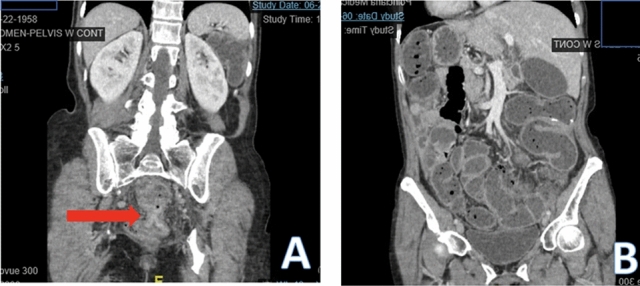

Methods: We present a 72-year-old male with prior radical cystectomy and neobladder creation complicated at the time by neobladder-cutaneous fistula and wound infection requiring revisional surgery and incisional hernia repair with mesh. He developed a large recurrent incisional hernia and underwent open hernia repair with bilateral anterior component separation, extensive lysis of adhesions, removal of prior mesh, and placement of a biologic mesh (Strattice™ RTM) in an underlay and onlay fashion. Intraoperatively, the defect measured 20 cm long by 14 cm wide. Postoperatively, he was treated for neobladder infection and CT cystogram found no extravasation from the neobladder. He presented to the emergency department 6 weeks after surgery with spontaneous partial midline wound dehiscence, with exposure of the onlay mesh and drainage of clear fluid, which was confirmed to be urine by fluid creatinine level. Repeat CT scan demonstrated a filling defect at the anterior wall of the neobladder with contrast leaking into a contained collection interposed between the anterior abdominal wall and the underlay mesh, extending superiorly between the small bowel loops and dehiscence of the midline abdominal wound. The patient was treated with a course of antibiotics and indwelling Foley catheter and bilateral nephrostomy tubes for urine diversion.

Results: Three months later, repeat CT cystogram demonstrated resolution of the leak and the nephrostomy tubes and Foley catheter were removed. The patient has continued daily wound care with significant reduction in size of the midline wound and increasing granulation tissue around the onlay mesh. He has not required further admissions to hospital and there has been no hernia recurrence so far.